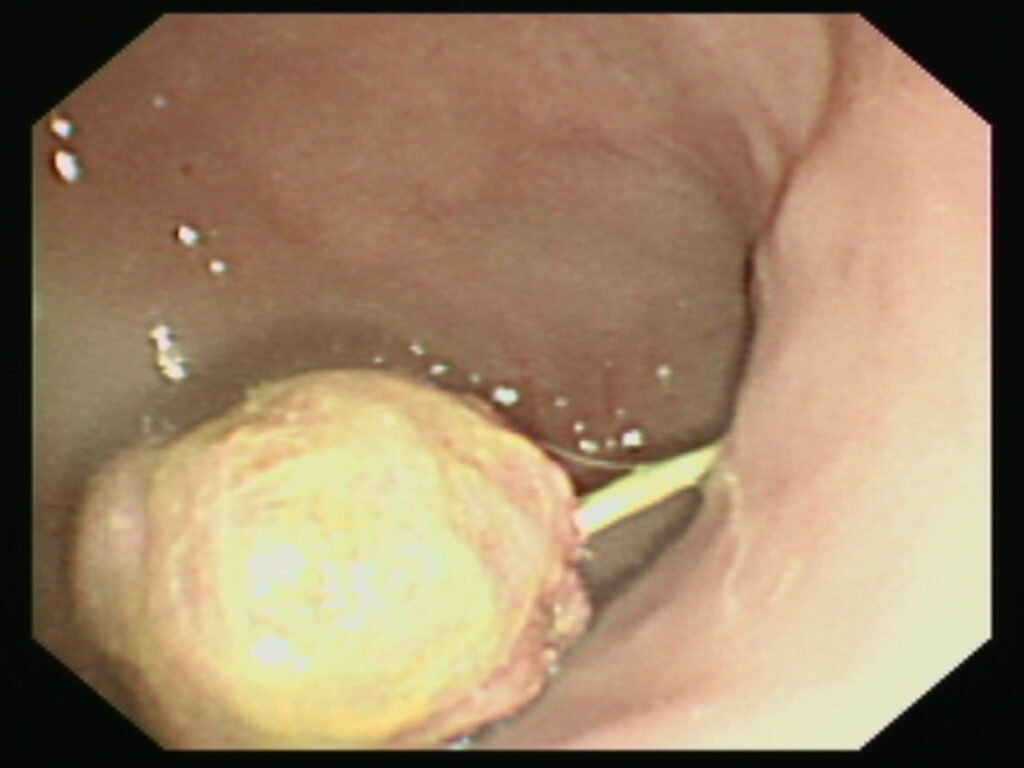

胃の中を内視鏡で見てみると、胃の出口に丸い異物がありました!

問診では丸い異物の情報はなかったのでひも状異物がクシャっと丸まっているのかなと想像していましたが、エコー検査で見た通りのしっかりと丸い異物が見つかりました。

おそらく丸い異物から紐が出ていて腸のほうに伸びているので丸い異物をつかんで慎重に引っ張てみます。

が、引っ張っても腸に流れた紐がびくともせず、あまり無理をするとひもの剪断力で腸が傷ついてしまう可能性があるため、開腹手術に切り替えました。